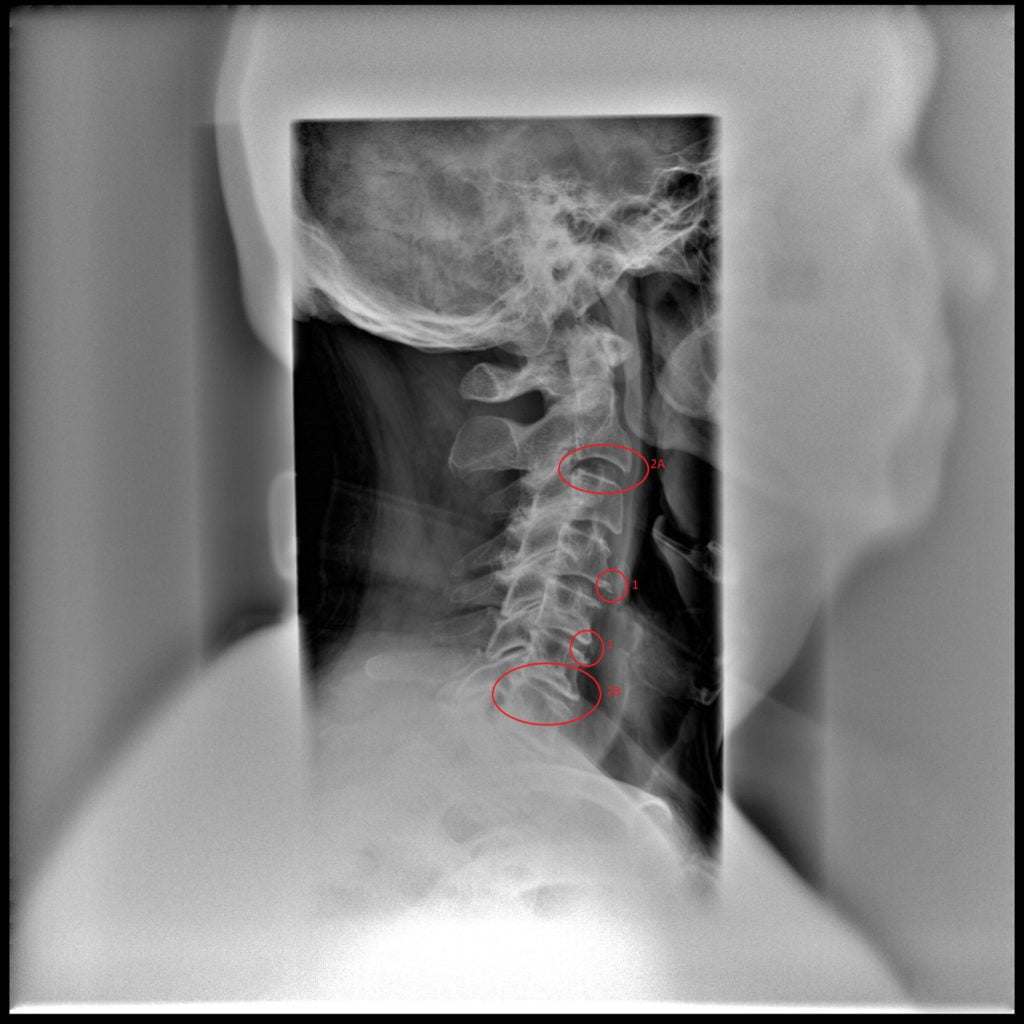

Йога при остеохондрозе шейного отдела позвоночника: какова эффективность?